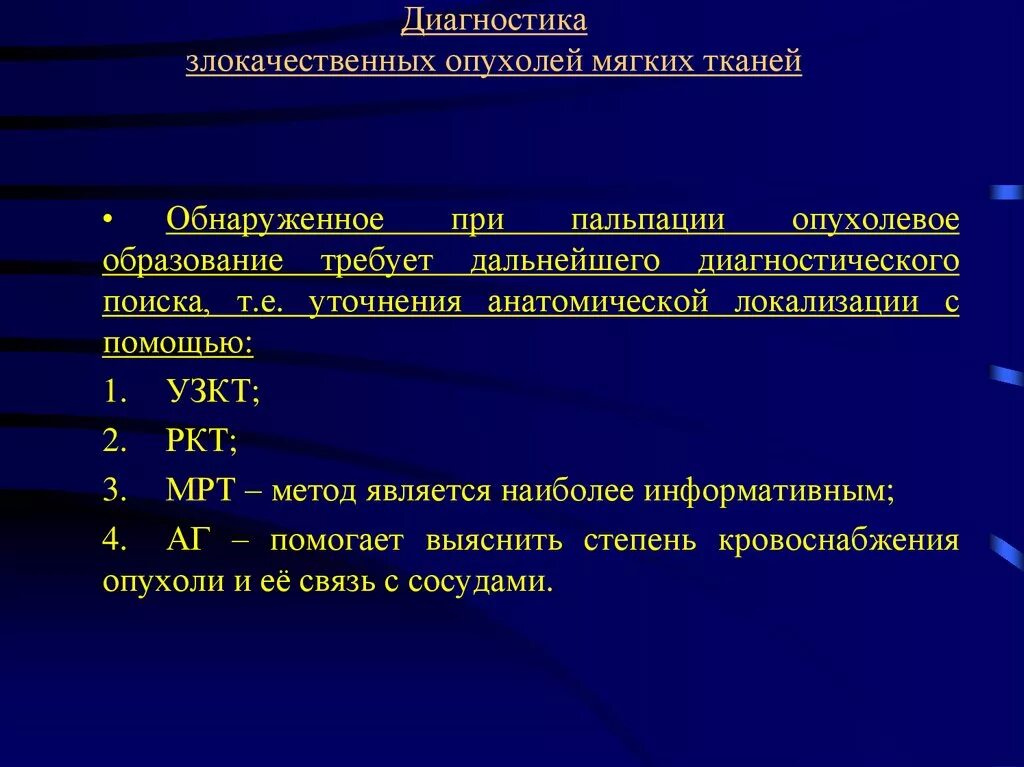

Понятие онкологической настороженности. Онкологическая настороженность в стоматологии презентация. 7 «Сигналов» злокачественной опухоли. Настороженность по онкологии. Алгоритм диагностики опухолей. Методы диагностики опухолей костей. Методы выявления опухоли. Методы диагностики злокачественных опухолей.

Алгоритм диагностики опухолей. Методы диагностики опухолей костей. Методы выявления опухоли. Методы диагностики злокачественных опухолей. Методы диагностики опухолей. Метод диагностики опухолей. Методы выявления опухоли. Методы диагностики злокачественных опухолей.

Методы диагностики опухолей. Метод диагностики опухолей. Методы выявления опухоли. Методы диагностики злокачественных опухолей.